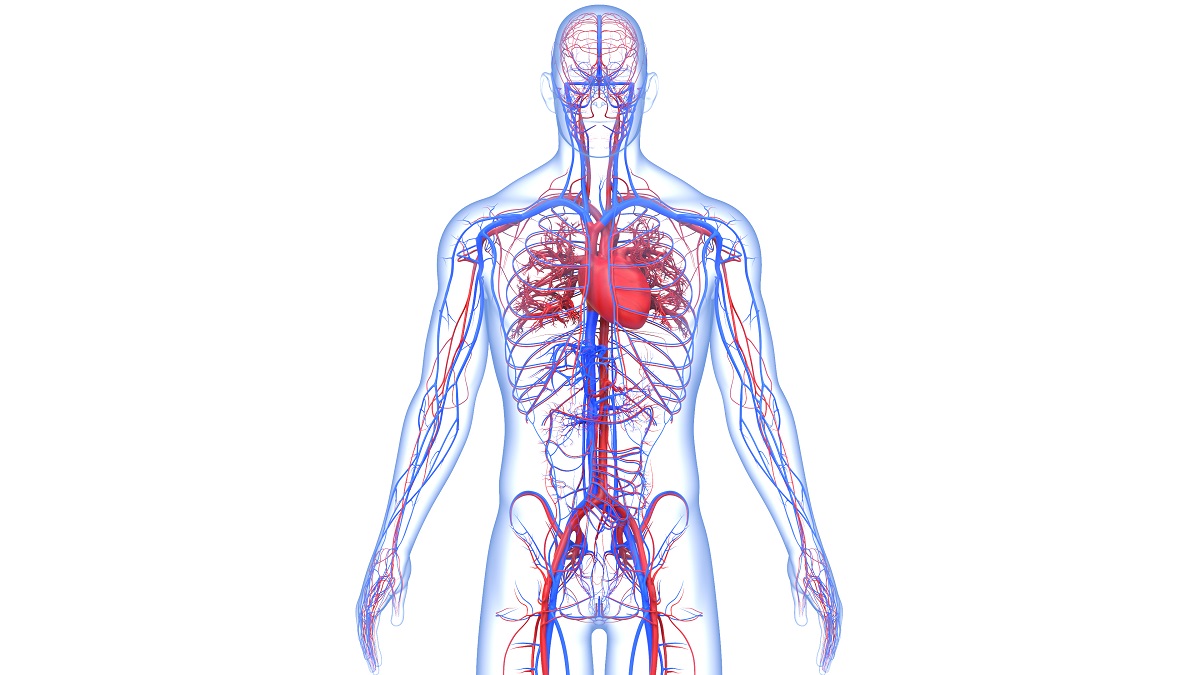

Anatomy of the Cardiovascular System

Think of your vascular system as the body’s plumbing system of vessels that are attached to your heart and carry blood throughout your body. The vascular system includes these vessels:

- Arteries, which carry oxygen-rich blood and nutrients from your heart to your tissues by way of your capillaries. The main artery from your heart is the aorta — your “water main.”

- Veins carry blood containing carbon dioxide and waste away from the tissues of your body and then return the blood to your heart.

- Capillaries are the tiny tubal links between your tissues and your small veins and arteries.

The term cardiovascular includes the vascular system plus the heart. A common cause of cardiovascular disease is the buildup of plaque (fat and cholesterol) that narrows or completely blocks the flow of blood in your arteries or veins.